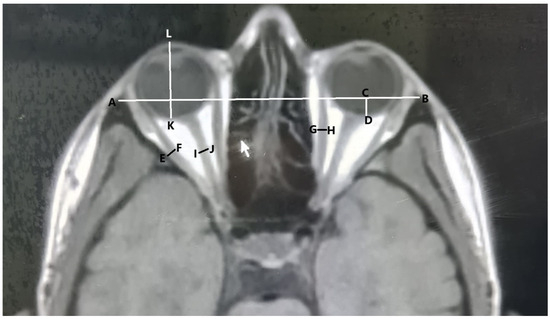

- The length of the interzygomatic line: This line was measured on axial images at the mid-globe position (Figure 1).

- Globe position: The distance between the interzygomatic line and posterior margin of the globe. It was measured perpendicular to the interzygomatic line on axial images in the mid-globe position (Figure 1).

- Ocular bulb length: The distance between the posterior surface of the cornea and posterior pole of the ocular bulb was measured in the mid-globe position on axial images (Figure 1).

- Optic nerve sheath diameter: Optic nerve sheath diameter was measured in axial sections from the area where the middle part of the nerve was visible, cutting the nerve course perpendicularly (Figure 1).

- The diameters of the lateral and medial rectus muscles: The horizontal diameter was measured from the widest area in the axial scans (Figure 1).